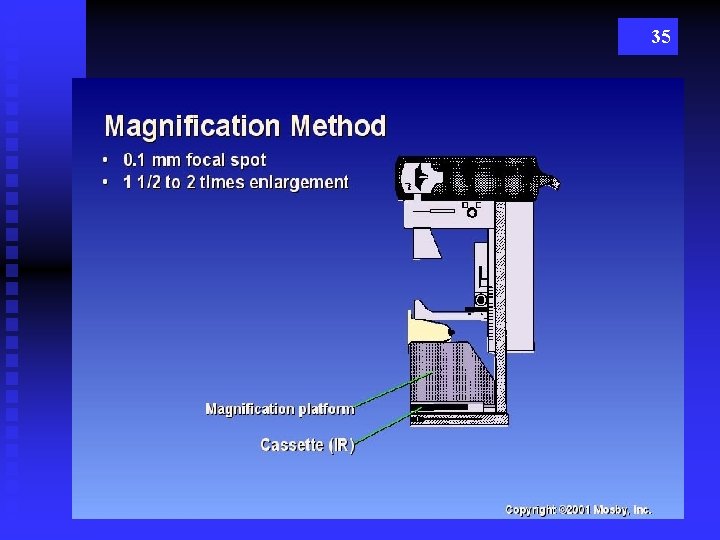

35

36 Magnification = increase OID